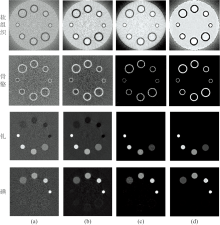

实验设计仿真模体包含软组织、 骨骼、 碘和钆四种材料, 其中背景区域的大圆代表软组织, 标号为2、 3、 4、 5的小圆分别为0.2%、 0.4%、 0.6%、 0.8%浓度的碘造影剂, 6、 7、 8、 9的小圆分别为0.1%、 0.2%、 0.3%、 0.4%浓度的钆造影剂, 小圆外围的灰色圆圈部分为不同厚度的骨物质。 仿真模体图如图1所示, 模体大小为10mm× 10mm, 分辨率为256× 256。 本实验运用SpekCalc软件来模拟管电压为120 kVp时的源能谱, 设定X射线源到旋转中心的距离为100 mm, 探测器的长度为20 mm, 且探测器单元数为320个, 单次扫描在[0, 2π )范围内均匀采集360个角度的投影数据。 120 kVp下的归一化能谱如图2所示, 依据四种材料的K-edge值及能量衰减特性, 将此宽能谱划分为4个能量通道进行模体仿真实验, 分别为: [16, 28]、 [30, 41]、 [50, 80]和[80, 120] keV。

本文经过多次实验调整, 将分解的参数设置为: α =1, 针对不同材料调整λ =[0.001 0.005 0.000 3 0.000 9], k1=50, η =0.05, k=10。 重建的参数设置为: γ =[0.06 0.06 0.04 0.04], k2=30。 在5× 105光子数下, 利用LS算法、 SR-TF算法和本文所提出的TV4算法对模体进行投影域材料分解, 其分解投影图如图3所示。 分解出的四种物质的投影图从上到下依次对应为软组织、 骨骼、 钆和碘, 从左到右依次为LS、 SR-TF和TV4算法的分解去噪结果。 由图3分解结果可以看出LS、 SR-TF和TV4算法都可以将四种物质分解开。 SR-TF算法的分解结果比LS算法包含更小噪声, 而TV4算法分解的四种物质的噪声最小, 抑制噪声效果最明显, 尤其在骨骼分解投影图表现最为突出, 体现了本文提出的TV4算法在投影域分解方面去噪效果的有效性。

图4(a— d)是分别在不同步骤上加入正则化获得的四种基材料图像结果。 从左到右依次为PD-MR方法、 TV4-MR方法、 PD-TV4方法作为对比方法和本文提出的D-TV4方法。 从图4中可以看出, 在PD-MR结果中软组织和骨骼图像受到严重的噪声污染, 其细微结构和特征被噪声淹没; 钆和碘图像重建过程中还产生了条纹伪影的干扰, 且碘中存在少量骨物质的串扰, 分解准确性降低。 与PD-MR方法相比, TV4-MR方法和PD-TV4方法能够提供更好的材料图像质量。 在TV4-MR结果中, 分解中的噪声得到了部分抑制, 但在重建时图像特征周围伪影严重, 这是由于SART重建的图像引起伪影, 最终的分解结果受到影响。 PD-TV4结果中, 钆和碘图像的伪影被有效去除, 但分解步骤受到严重噪声的干扰, 骨骼图像的边缘结构未能准确分出。 然而, D-TV4方法可以进一步提高材料成分的准确性, 四种物质的分解结果都得到很好的噪声伪影抑制效果且物质边缘细节结构清晰。 由于D-TV4继承了PD-TV4和TV4-MR的优点, 它在材料分解和重建中可以进一步提高材料精度, 进而获得高质量的基材料图像。

为了定量分析D-TV4方法提高材料分解精度的性能, 利用PSNR计算其分解质量和RMSE计算其分解误差, 实验的量化结果如表2所示。 对表2的数值比较可知, 相比于对比方法, D-TV4对于每种基材料总能实现最高PSNR和最小RMSE值。 通过数值比较, 进一步证明了在分解和重建步骤的双正则化可以提高材料分解的精度。